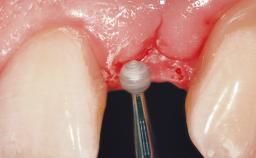

A 33-year-old female patient presented with an upper left central incisor that required extraction after a failed endodontic therapy. The tooth had been traumatized when the patient was a teenager and had undergone several endodontic treatments, including two apicectomy procedures. The patient was in good health and did not smoke. Clinical examination showed that the patient had a high lip line. In full smile, the gingival margins of the upper teeth were visible to the first molars. The gingival margins of central incisors 11 and 21 were only just showing. Examination of tooth 21 confirmed that the tooth was mobile and had hypererupted by 1 mm.

Placement Protocol Immediate implant placement

Socket Integrity Damage to one or more bone walls

Bone Volume Damage to one or more socket walls